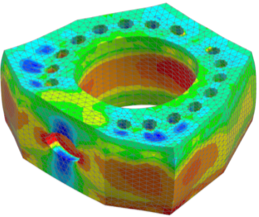

– biomechanické numerické simulácie a skúšky digitálnych modelov implantátov z materiálu PEEK a jeho derivátov korešpondujúcich s reálnymi vyrobenými modelmi,

Obr. 6 Numerické biomechanické testovanie cervikálnych implantátov v rámci simulácií